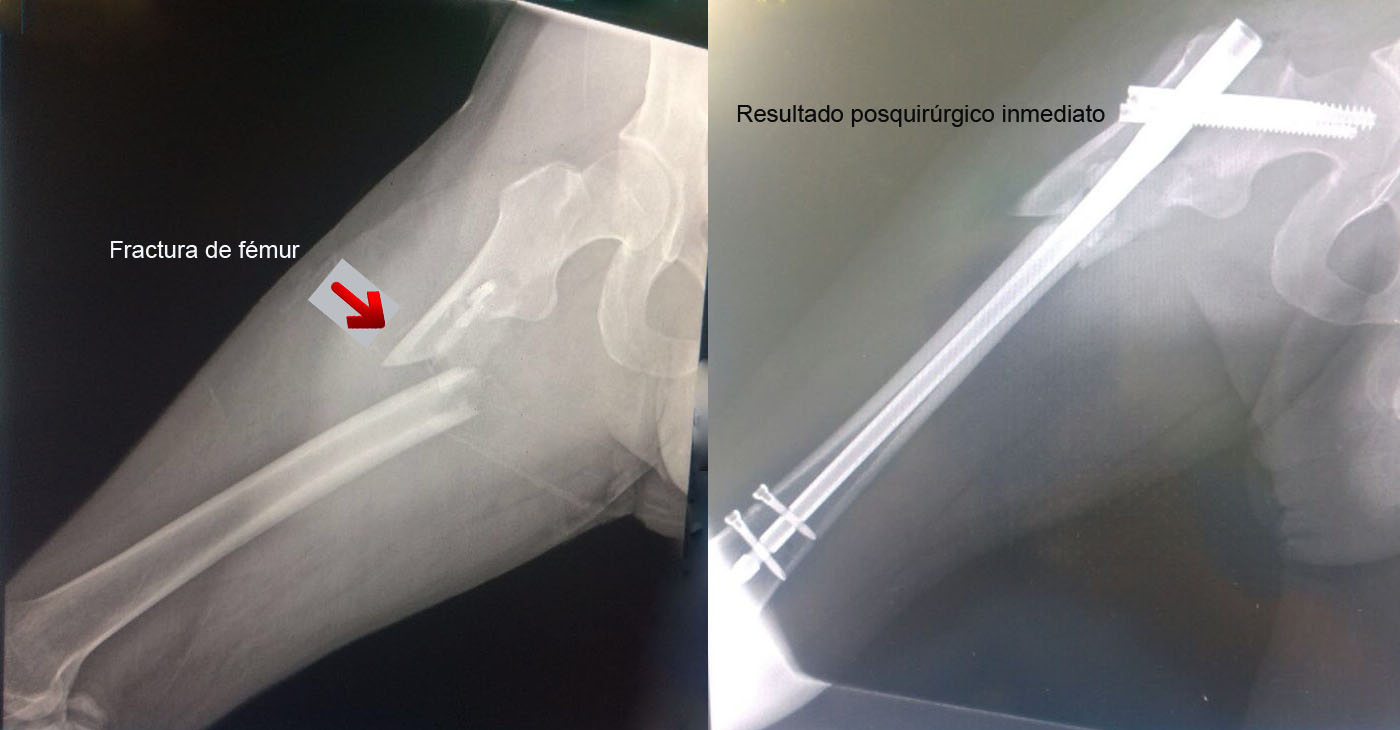

Una fractura ósea es la ruptura de un hueso, la cual puede presentarse por diversas causas y su tratamiento dependerá de la magnitud, sitio anatómico y de las enfermedades concomitantes. Algunas pueden manejarse de forma conservadora con solo inmovilización y hay otras que requieren de un tratamiento quirúrgico. A continuación, podrá ver algunos casos quirúrgicos, dando clic a la zona del cuerpo afectada.